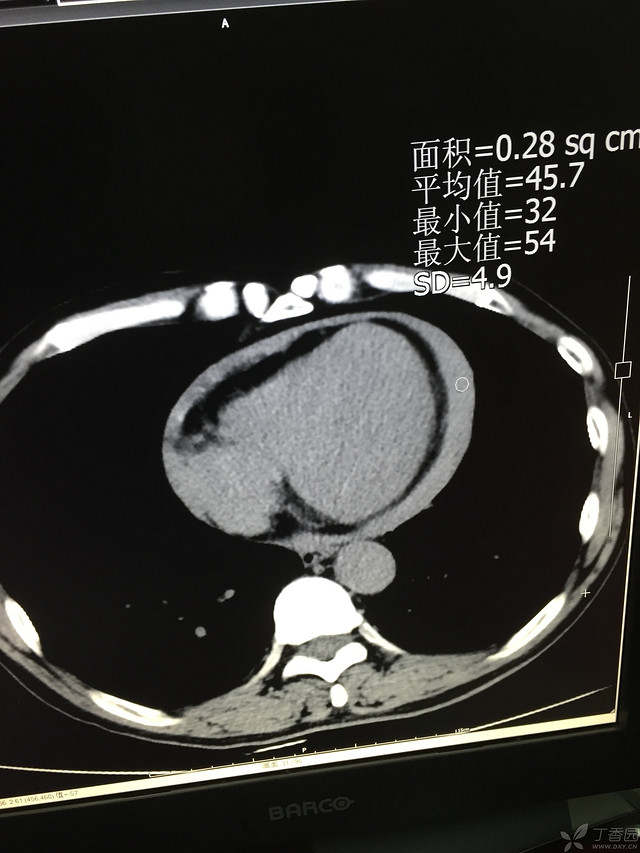

胸痛三天,加重三小时(CT是心包高密度影是什么)

患者性别:男

患者年龄:64岁

简要病史:三天前休息时突发胸前区疼痛伴大汗,到当地医院输液治疗后缓解,3小时前情绪激动后再次出现胸痛伴大汗,胸部压迫感,持续不缓解入院,到当地医院测血压180/?mmHg泵入硝酸甘油转入我院。

体格检查:血压94/72mmHg(右侧)96/74mmHg(左侧),心率78此/分,其他未见阳性体征